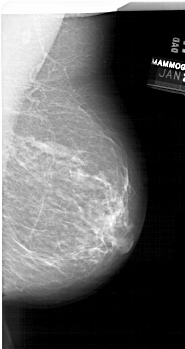

A_1679_1.LEFT_CC

LEFT_CC LINES 6631 PIXELS_PER_LINE 3346 BITS_PER_PIXEL 12 RESOLUTION 43.5 OVERLAY